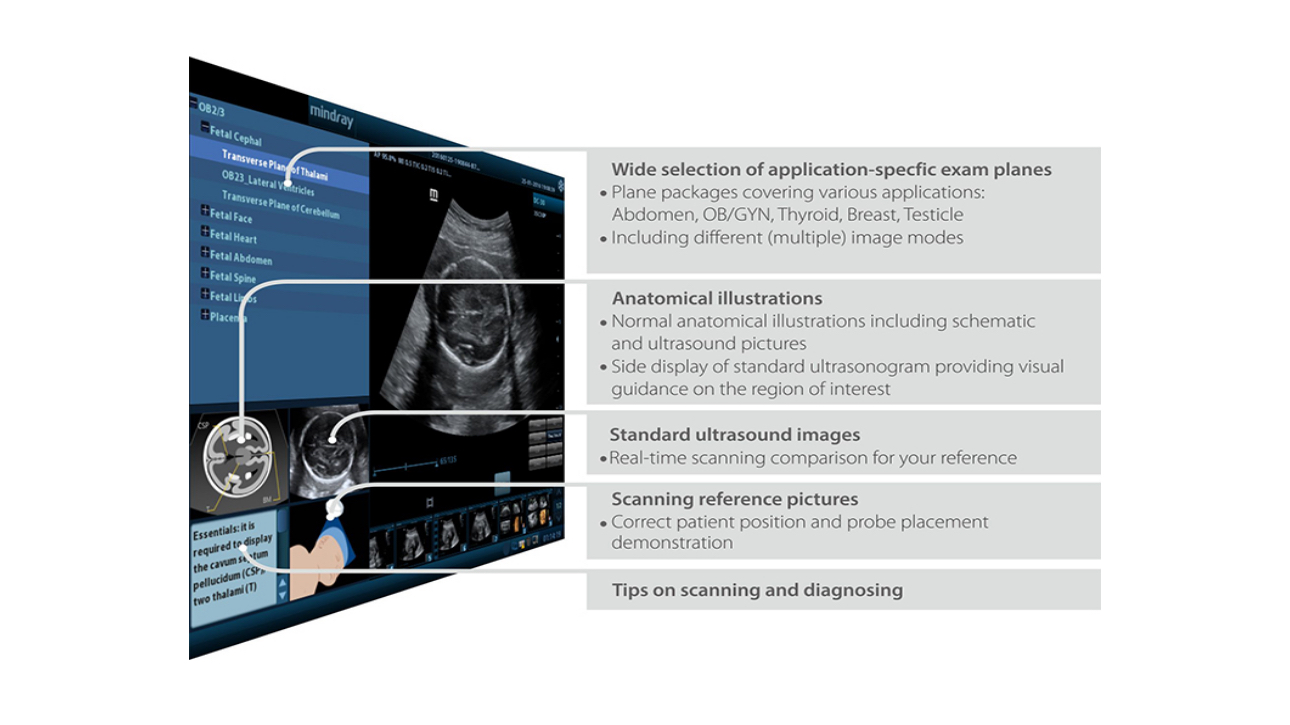

iScanHelperTM

Dedicated inbuilt tutorial software.

┬Ę Anatomical diagram illustrations including schematic and ultrasound picture

┬Ę Standard ultrasonogram comparison with real-time scanning

┬Ę Scanning reference picture demonstrating appropriate patient position and probe placement

┬Ę Tips on scanning skills and diagnostic information